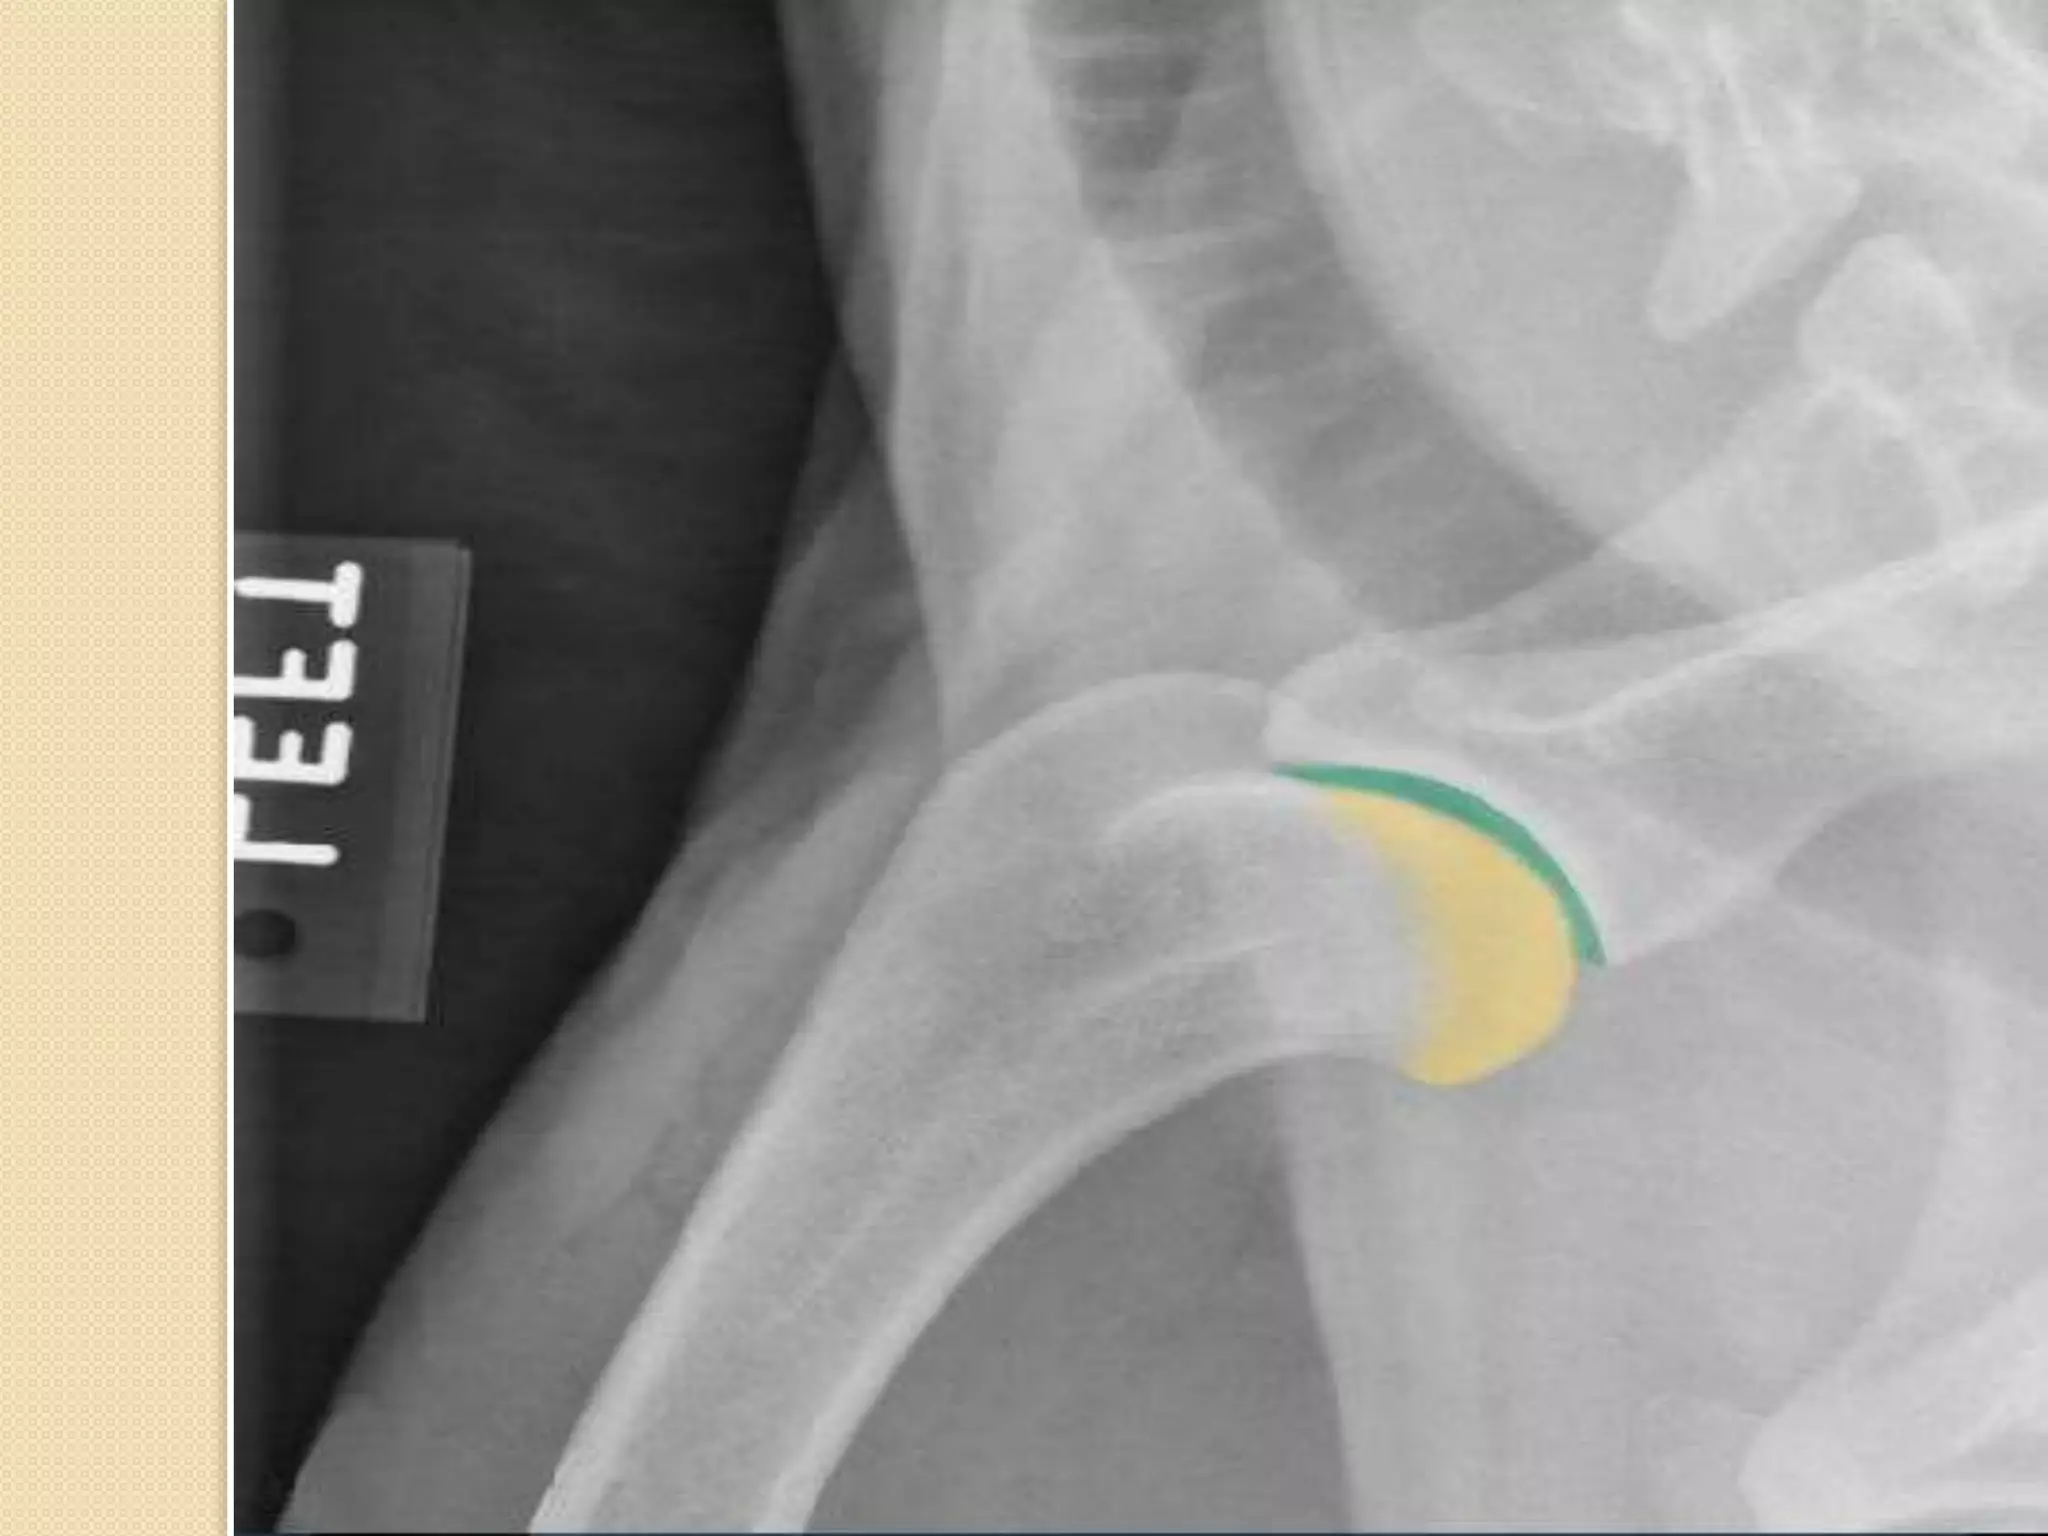

Hip joint:

Hip joint is formed of the head of the femur

Femur : It isa long bone which form the thigh region. The head of the femur form the hip joint with the acetabulum of the os coxae . The caudal surface characterized by 2 rough lines diverge proximally and distally towards the extremities called linea Aspera The present of the supracondyloid facets.

Hip joint: Hip jointis formed of the head of the femur with the acetabulum of os coxae.